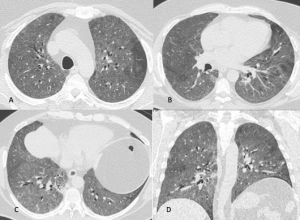

Figura 13: Uomo di 45 anni giunge in Pronto Soccorso per IRA e grave anemizzazione. La TCAR eseguita all’ingresso (scansioni assiali A-B-C e ricostruzione MPR sul piano coronale D) mostra la presenza in entrambi i polmoni di multiple aree di aumentata densità con aspetto in parte a "vetro smerigliato" ed in parte consolidativo con broncogramma aereo nel contesto e distribuzione simmetrica, prevalente in sede perilare con risparmio delle zone subpleuriche. In considerazione della clinica e della distribuzione delle lesioni l’ipotesi diagnostica formulata (in seguito confermata dal BAL) è quella di emorragia alveolare diffusa.

Figura 14: Paziente di sesso femminile, 75 anni, con storia di interstiziopatia polmonare inquadrata come UIP probabile dal 2018. La paziente giunge al Pronto Soccorso per repentino e grave peggioramento della funzionalità respiratoria. Le immagini TCAR assiali (A-B) documentano la presenza in entrambi i polmoni di multiple aree a “vetro smerigliato” con distribuzione diffusa. Dopo aver escluso le ipotesi di edema cardiogeno e di infezione polmonare viene posta diagnosi di esacerbazione di fibrosi polmonare idiopatica.